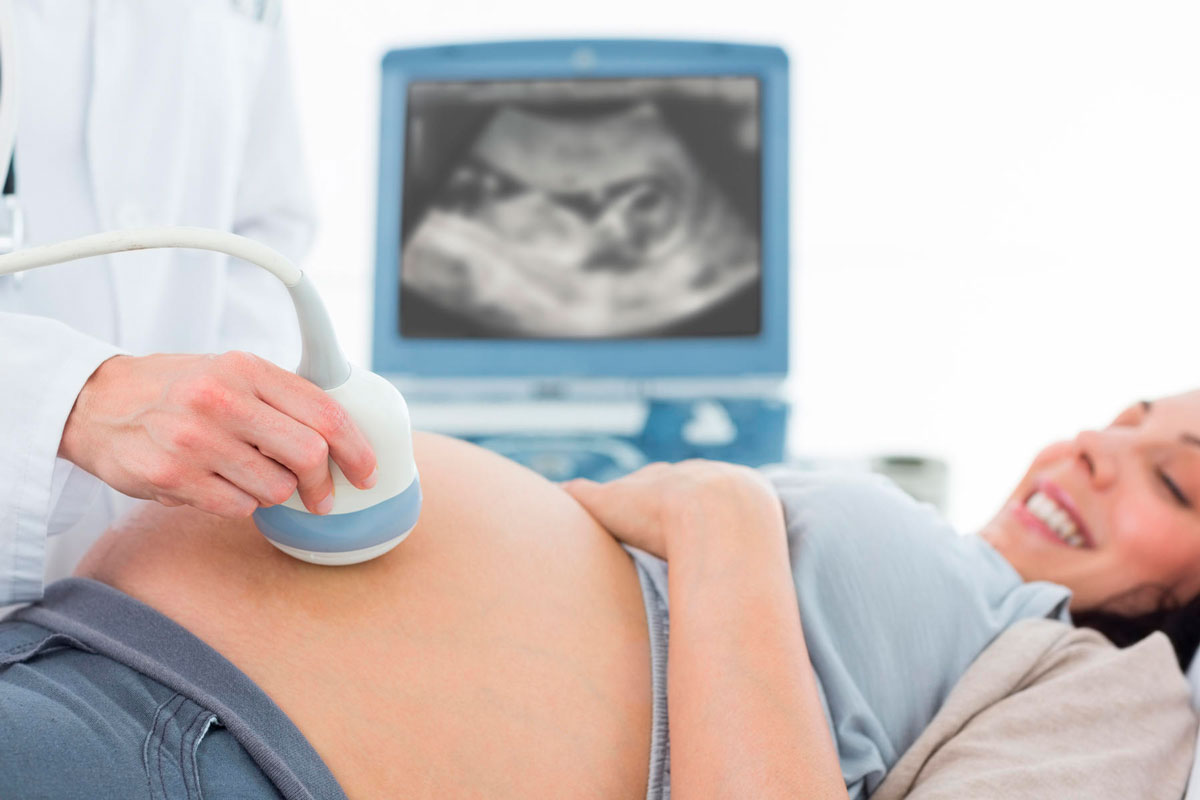

Ultrassonografia Obstétrica:

É um exame de imagem não invasivo e indolor, que utiliza ondas sonoras de alta frequência para visualizar a saúde e o desenvolvimento do feto durante a gestação.

O exame ajuda no estudo e acompanhamento, desde o começo gestacional, para identificação do número de embriões, acompanhamento do desenvolvimento fetal, rastreio de alterações morfológicas, passando por todas as semanas de gestação, para adequada avalição da vitalidade fetal.